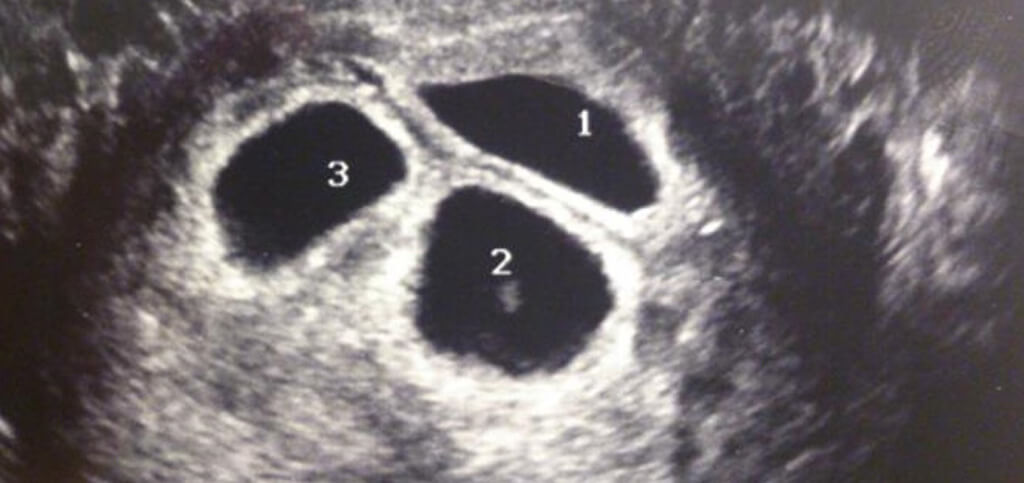

At the ultrasound appointment, Sarah and Andy would have a chance to see their new child for the first time. However, something strange showed up on the scan that displayed on the ultrasound monitor. Everything looked normal for the birth mom, but to her surprise and everyone else's, she was actually carrying three babies instead of one!

Sarah, Andy, and their birth mother were completely shocked to see three heartbeats on the ultrasound monitor. They have worked so hard for so long just to be blessed with one bundle of joy, but now the universe was giving them three.